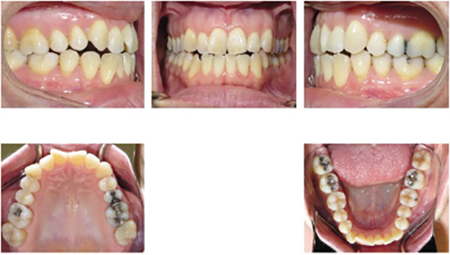

Conservative approach for the treatment of anterior tooth wear

The intention of this article is not to discuss all the factors involved in formulating a diagnosis and treatment plan for anterior tooth wear, but rather to demonstrate the favourable outcome one can achieve when implementing a minimally invasive treatment option. The option involves optimal orthodontic tooth positioning using a clear aligner system followed by … Read more